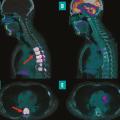

Avancées et intégration de la médecine nucléaire dans la pratique clinique

La médecine nucléaire, spécialité d’imagerie médicale en plein essor depuis cinquante ans, joue aujourd’hui un rôle important dans de nombreuses spécialités, telles que l’oncologie, la cardiologie ou encore la neurologie. Le principe de la médecine nucléaire repose sur l’utilisation de sources radioactives non scellées pour…